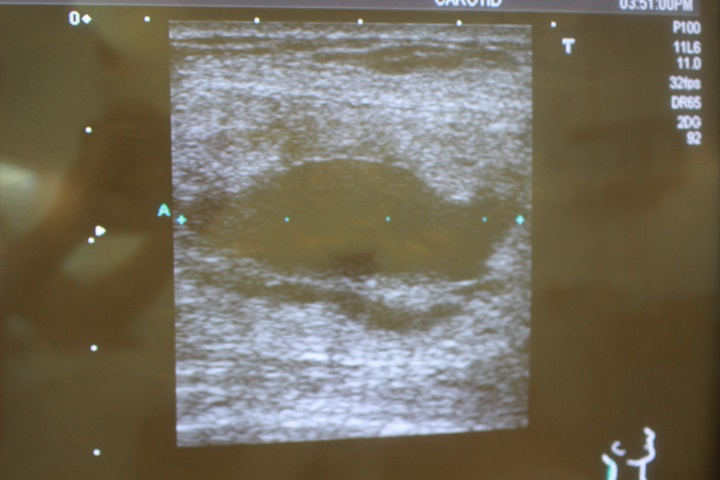

脂肪注入後のしこり除去

1年前に他院で脂肪注入による豊胸手術を受けたそうです。 術後3か月後くらいから硬くなってきて痛みもあるとの事で当院を受診され...